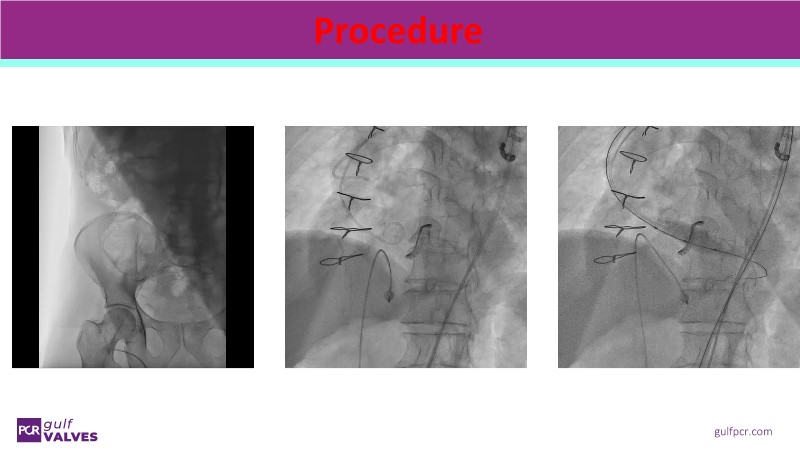

Join this comprehensive session to explore the Myval transcatheter heart valve series, featuring the latest clinical updates from two large randomized controlled trials—Landmark and Compare TAVI. Learn from real-world experiences, including recorded cases, and understand how these innovations translate to complex patient demographics in daily TAVI practice.